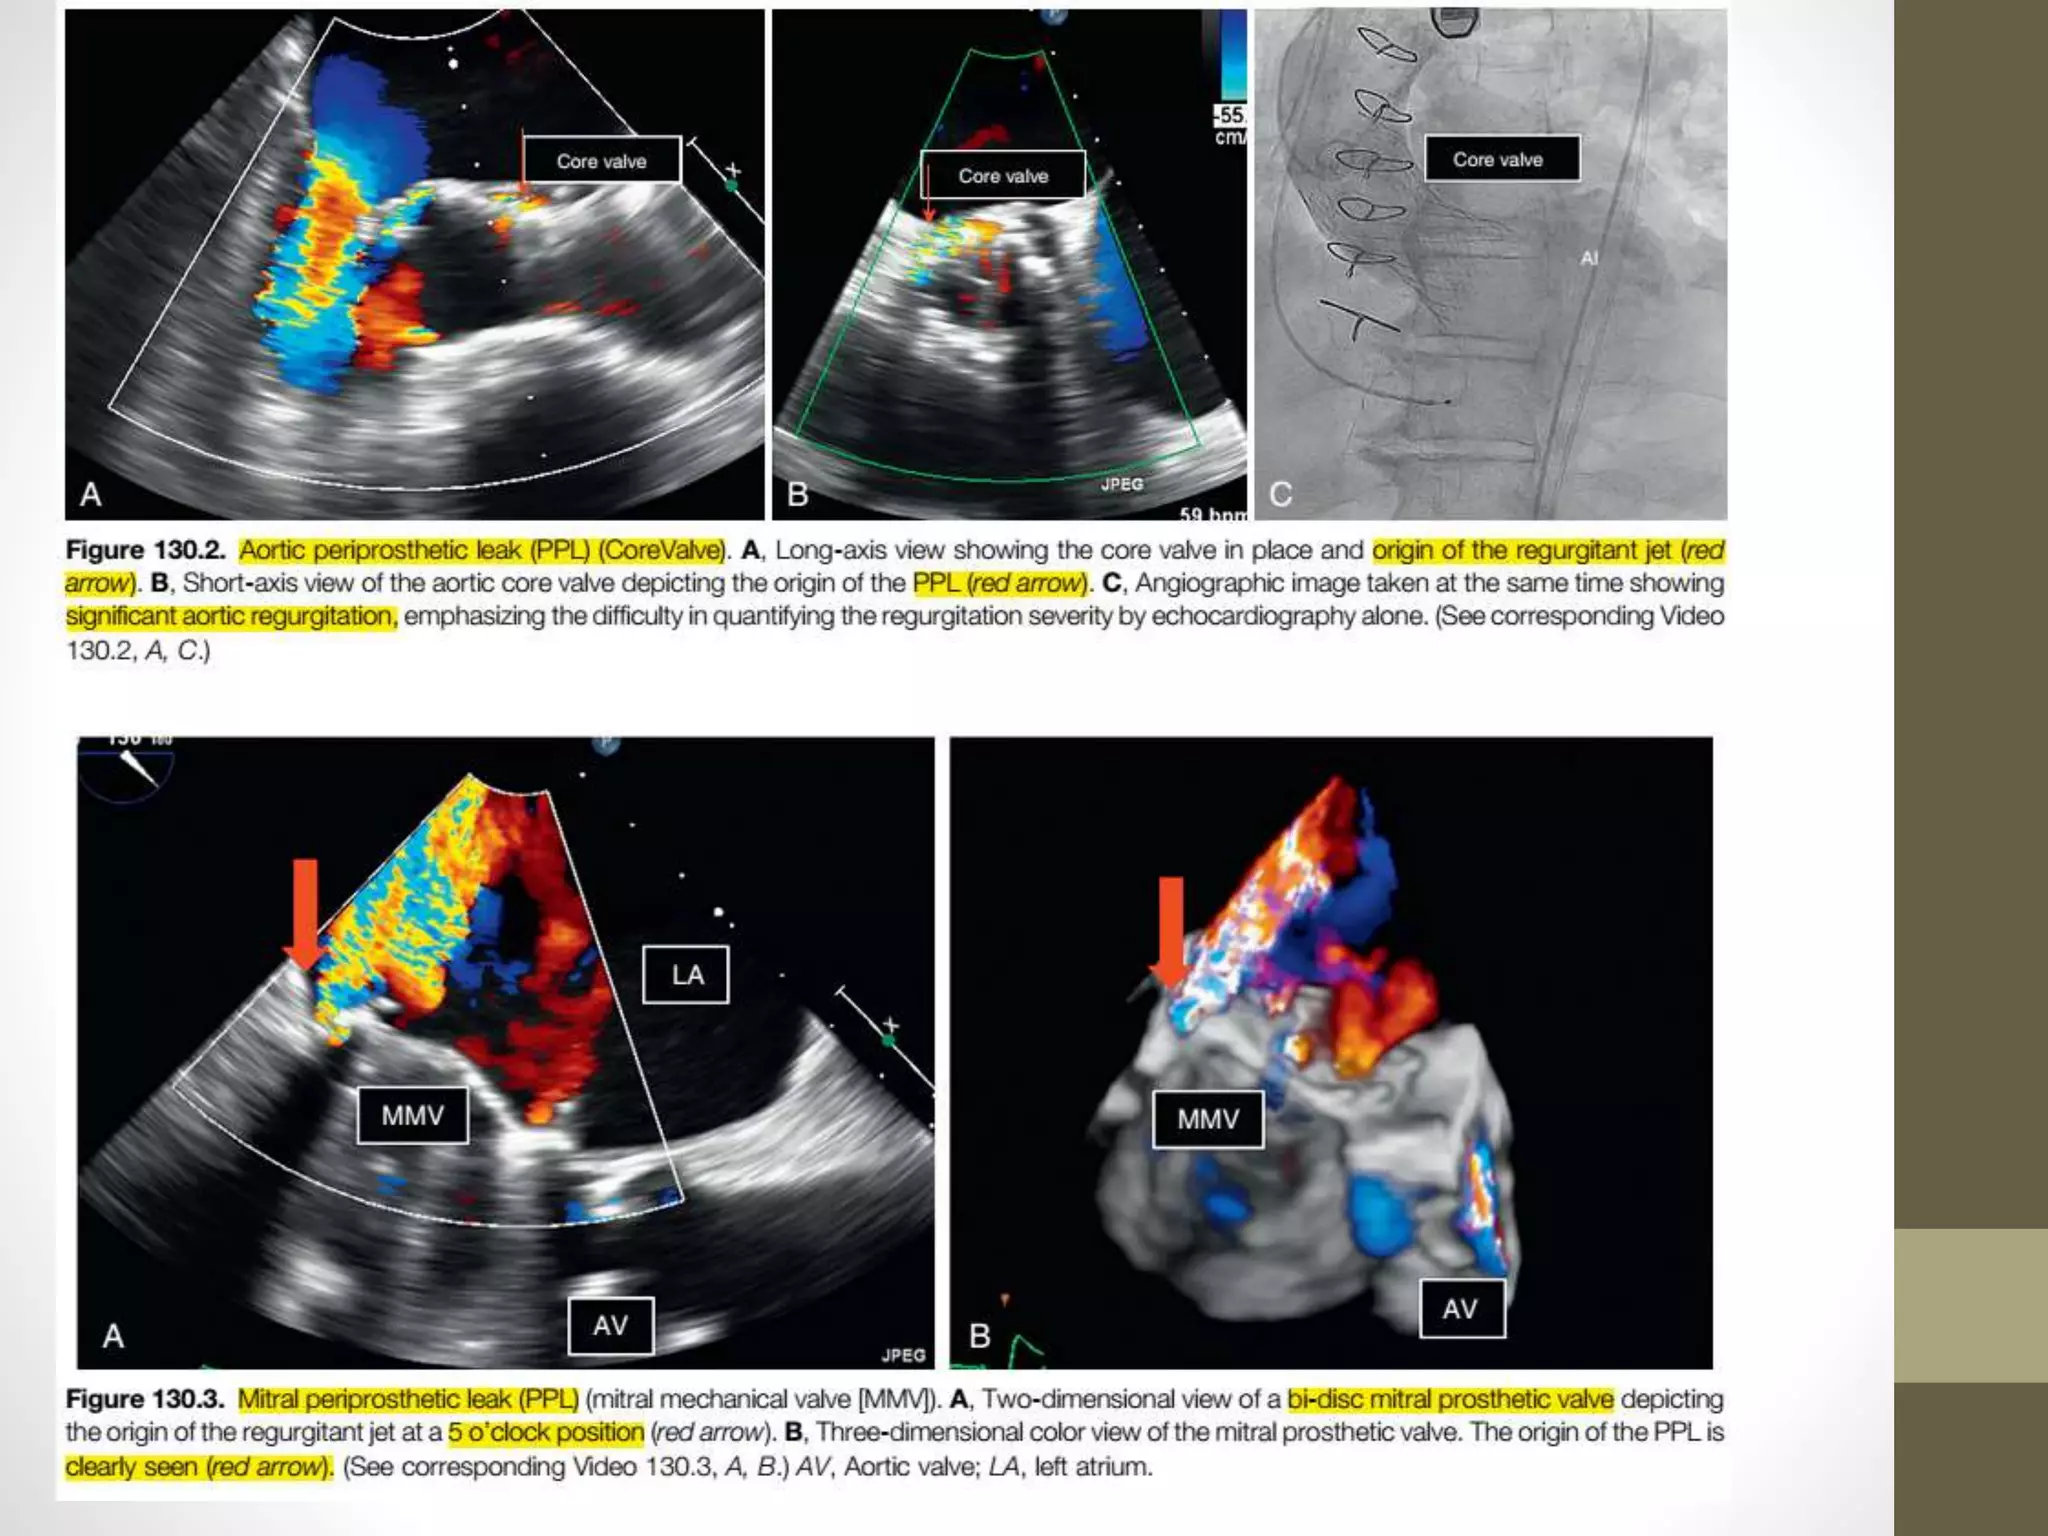

• The more anterior location of the aortic valve makes it visible

on TTE, and often the origin and severity of the paravalvular

regurgitation can be delineated by TTE.

• Aortic PPL jets tend to be eccentric and may flow in somewhat

unusual directions